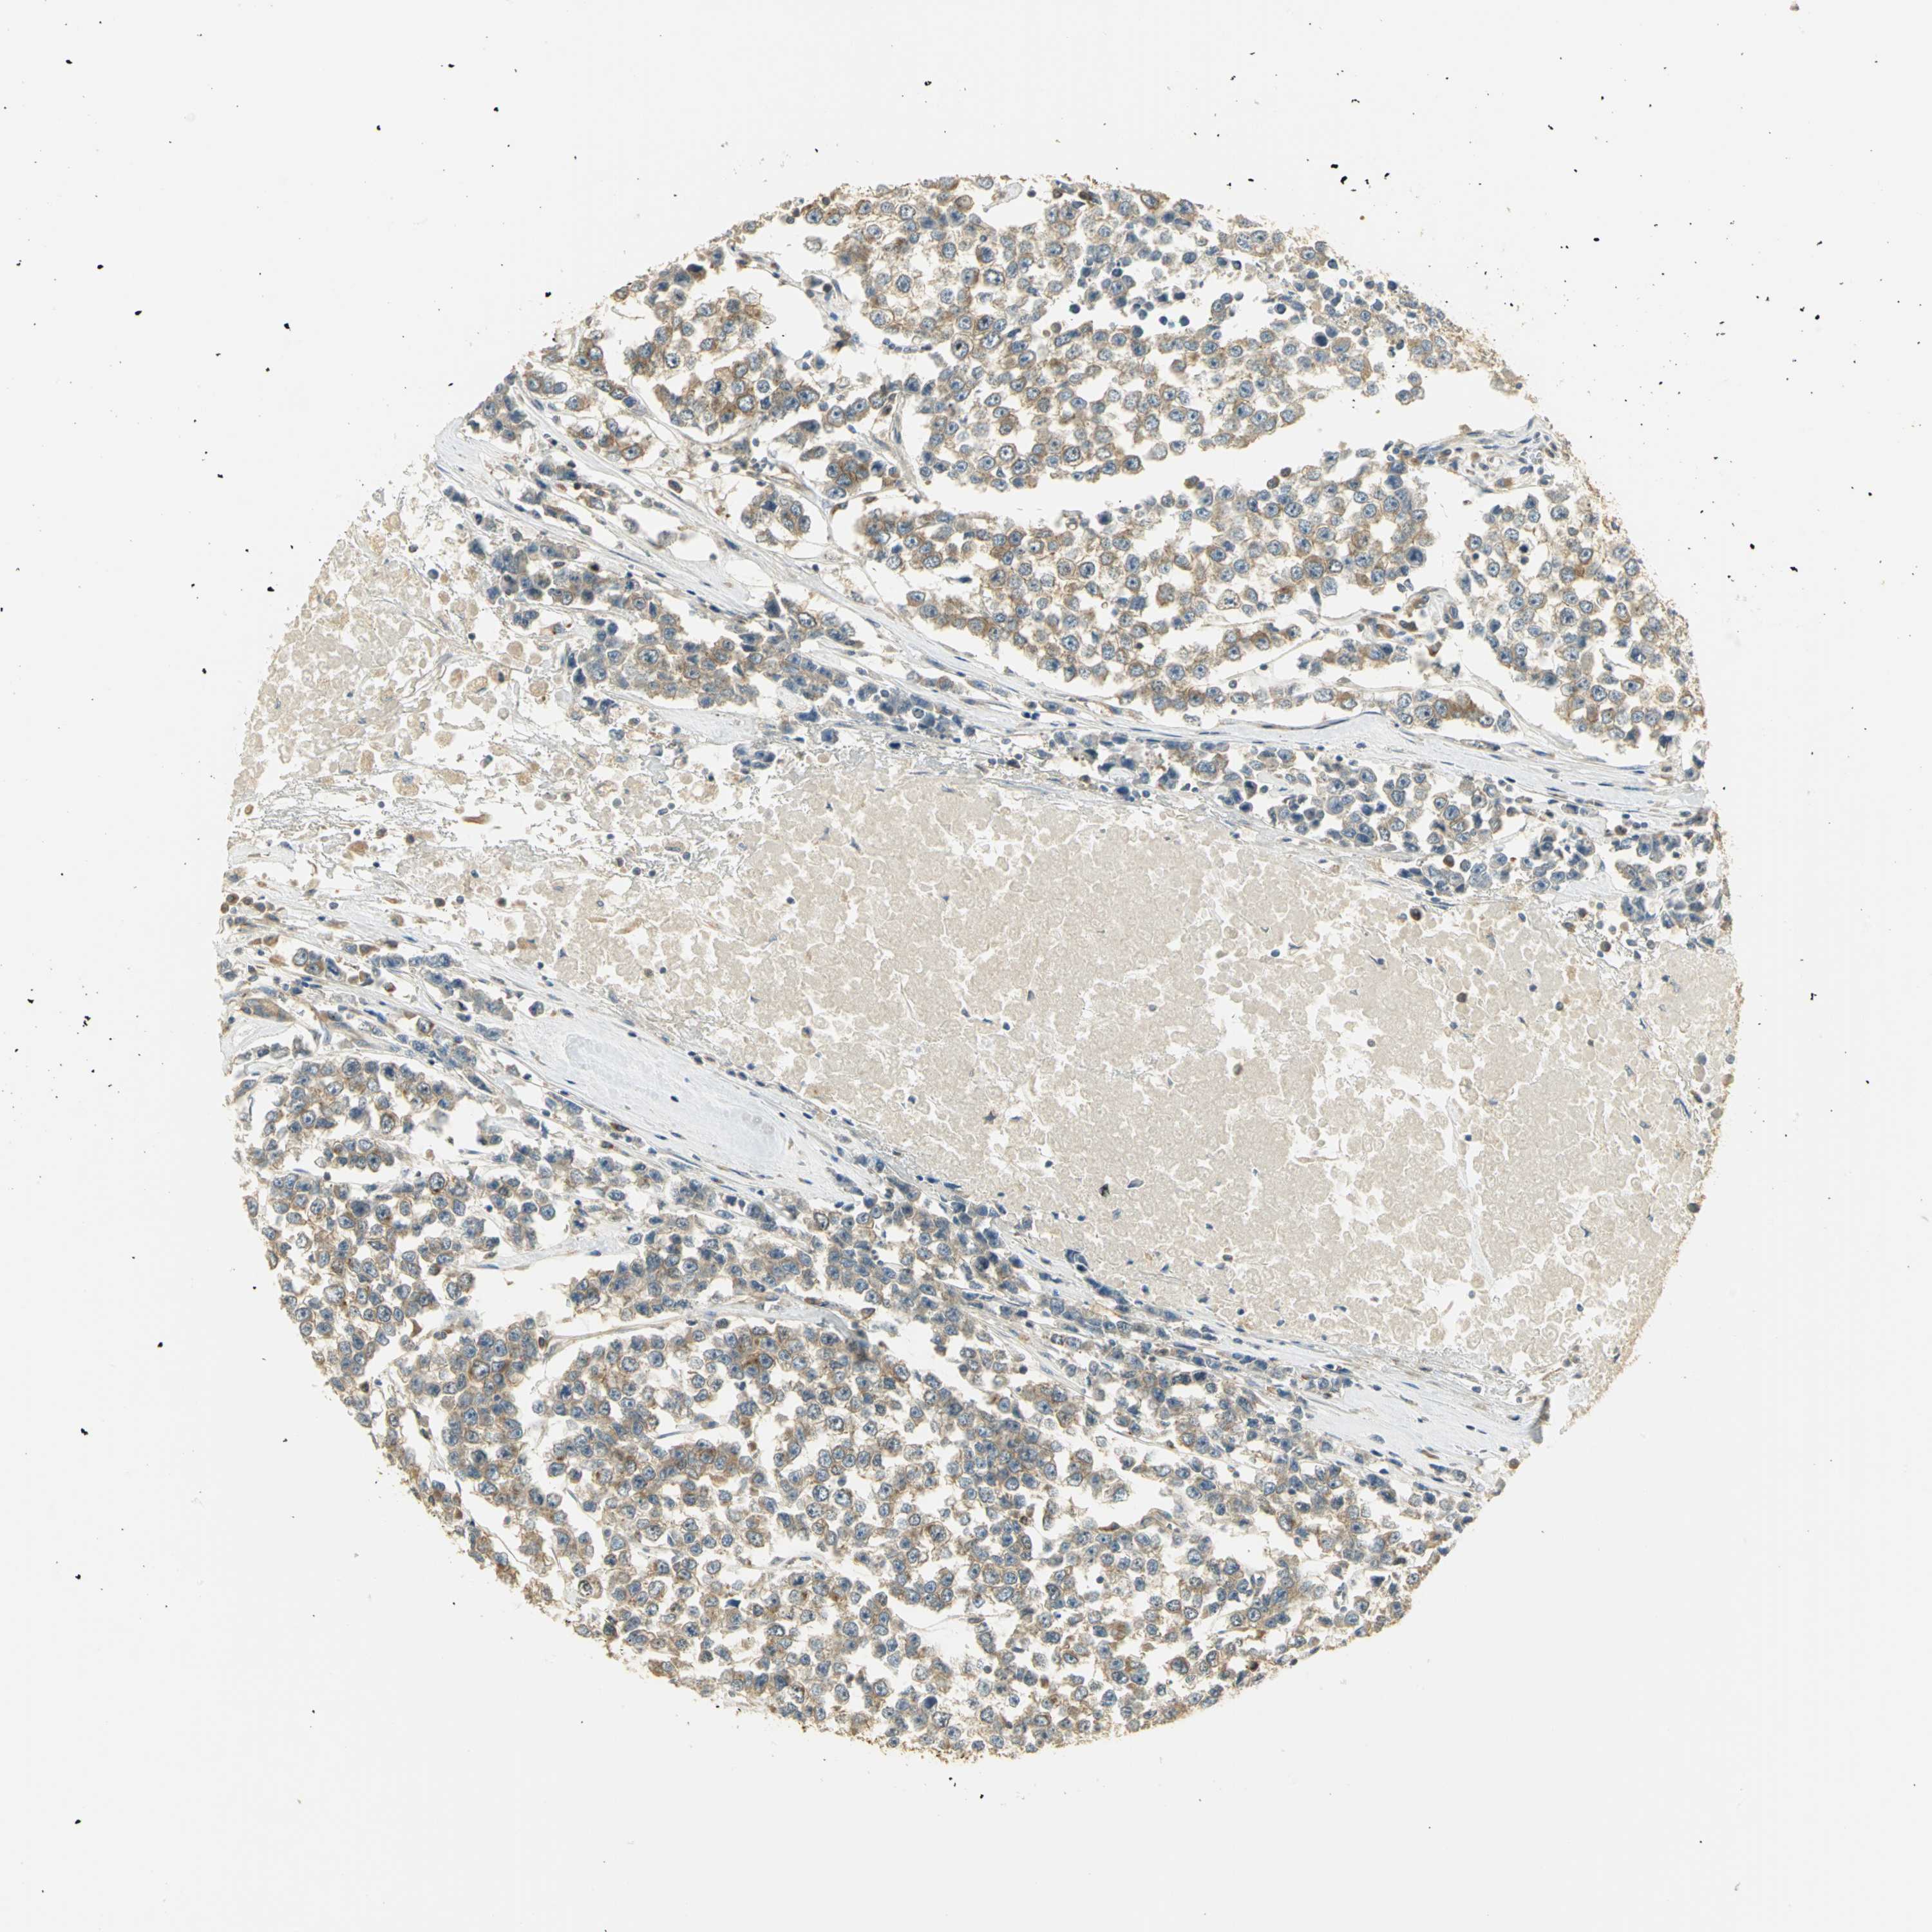

TESTIS CANCER - Protein expressioni

A mouse-over function shows sample information and annotation data. Click on an image to view it in a full screen mode. Samples can be filtered based on level of antibody staining by selecting one or several of the following categories: high, medium, low and not detected. The assay and annotation is described here.

Note that samples used for immunohistochemistry by the Human Protein Atlas do not correspond to samples in the TCGA dataset.

Antibody stainingi

Antibody staining in the annotated cell types in the current human tissue is reported as not detected, low, medium, or high, based on conventional immunohistochemistry profiling in selected tissues. This score is based on the combination of the staining intensity and fraction of stained cells.

Each image is clickable and will lead to virtual microscopy that enables deeper exploration of all samples and also displays staining intensity scores, fraction scores and subcellular localization as well as patient and tissue information for each sample.

Antibody HPA003979

Staining

High

Medium

Low

Not detected

Intensity

Strong

Moderate

Weak

Negative

Quantity

>75%

75%-25%

<25%

None

Location

Nuclear

Cytoplasmic/membranous

Cytoplasmic/membranous,nuclear

Carcinoma, Embryonal, NOS

Seminoma, NOS